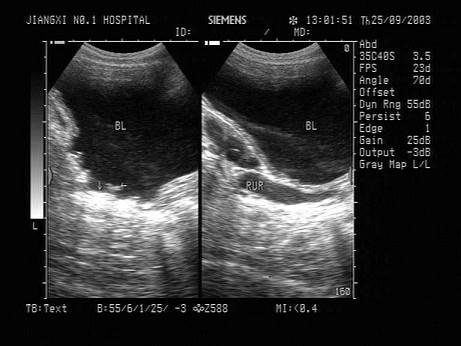

问题 男性,有前列腺增生病史,膀胱出现如图的超声表现,最可能的诊断为?(?)

选项 A.膀胱血块 B.膀胱肿瘤 C.膀胱憩室 D.膀胱小梁小房形成 E.慢性膀胱炎

答案 D